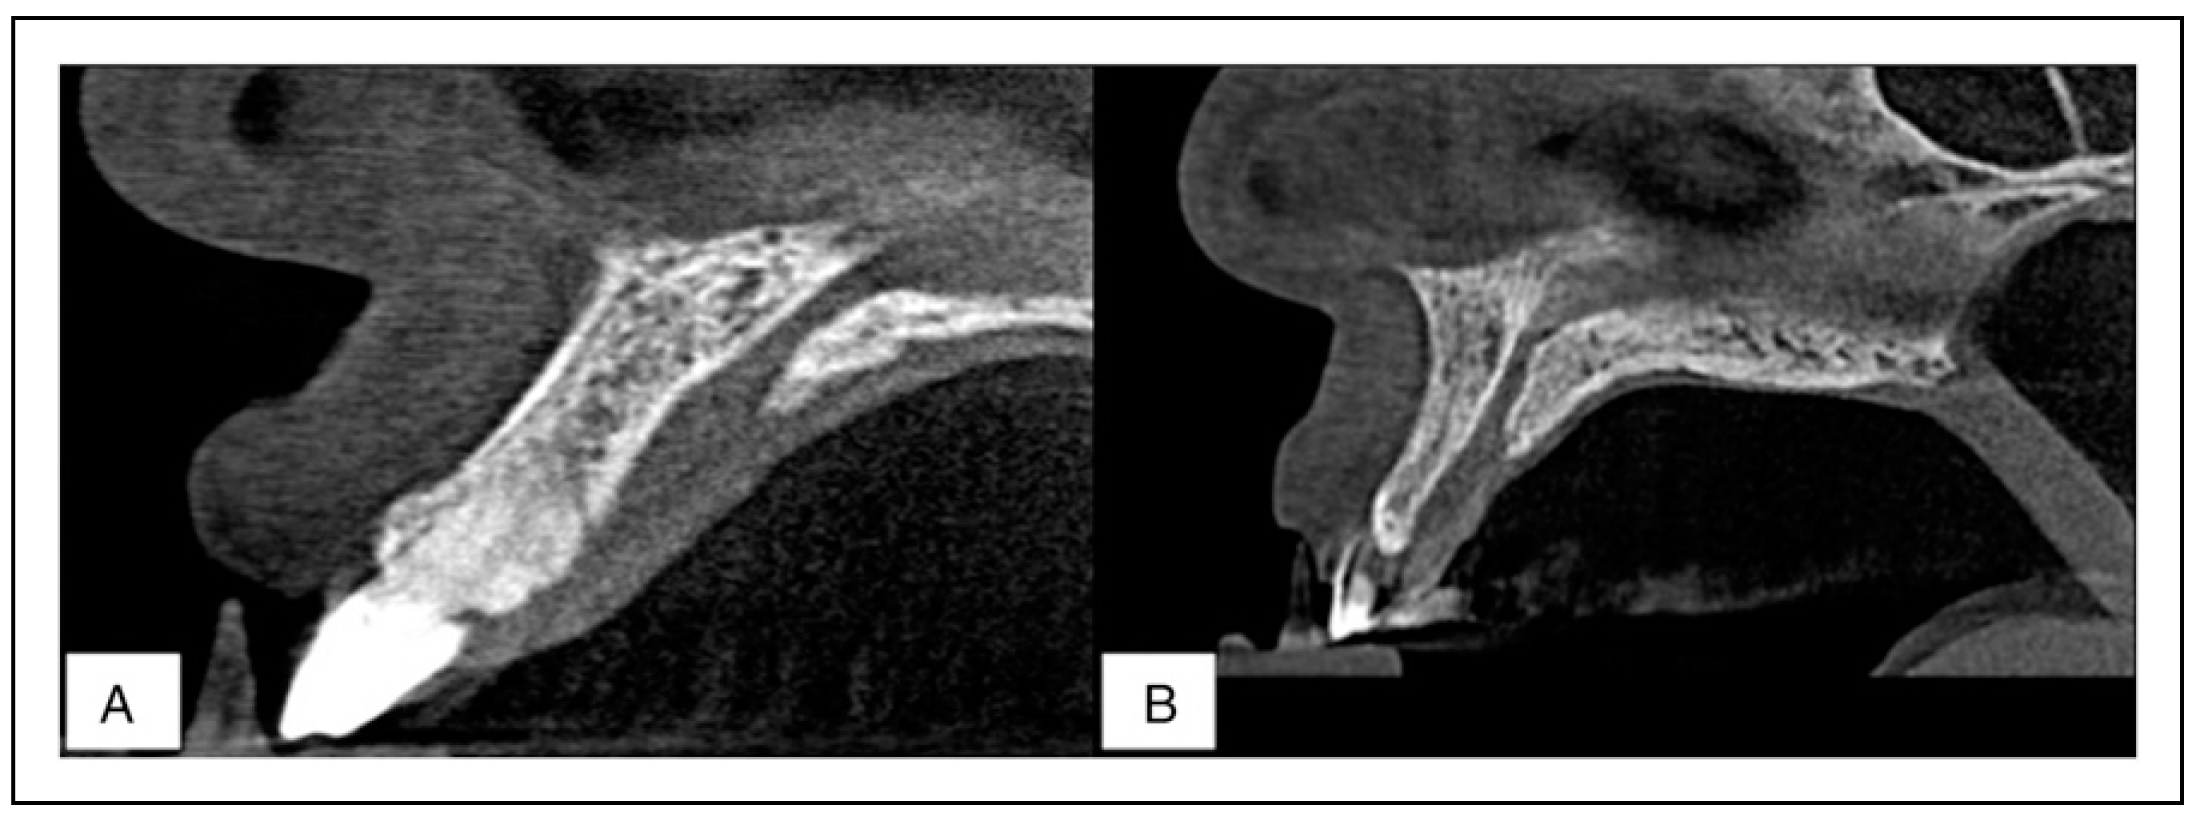

Maxillary Bone

The thickness of the maxillary bone anterior to the NPC was measured at 3 levels; at the nasal spine, at the mid-point, and the alveolar crest (Figure 1). In general, the results reveal that on average males had a thicker maxillary bone at all levels in comparison to females (Table 3).

However, only the mid-point thickness was found to be significantly higher in males (Independent t-test, P <.05). Lastly, the general trend observed was a reduction in the thickness of bone from the level of the nasal spine to the alveolar crest.

As pertain the shape of the maxillary bone, it was classified as either concave, convex, or flat (Figure 6). The results reveal that the flat shape was most prevalent among males while the concave shape was most prevalent among females. No convex shape was encountered in this study. These results exhibited sexual dimorphism (Chi-square test, P <.05). Furthermore, the angulation of the maxillary bone was found to be similar at an average of 116.00° to the horizontal plane in both males and females.

With regards to the shape of the maxillary bone, the majority of cases were found to be flat in males and concave in females. This data is scarce in literature; therefore, little comparison can be made. This finding concurs with the alveolar bone measurements observed at 3 levels of NPC. Therefore, clinicians should be vigilant during implant placement in women due to the concave shape of the bone, which has an increased risk of fenestration. The clinician may need to raise a flap when performing this surgery and shall be ready to graft this perforation when the need arises. Lastly, the angulations of the NPC and the maxillary bone were found to be 118.42° and 116.00° revealing that they are relatively parallel to one another, thus an implant can be inserted along the long axis of the bone.

Figure 6. Sagittal CBCT sections of the maxillary bone both the flat (a) and concave (b) shapes encountered in the present study.